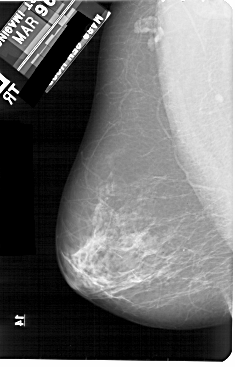

A_1908_1.RIGHT_MLO

LEFT_CC LINES 5461 PIXELS_PER_LINE 3166 BITS_PER_PIXEL 12 RESOLUTION 43.5 NON_OVERLAY

RIGHT_CC LINES 5491 PIXELS_PER_LINE 2971 BITS_PER_PIXEL 12 RESOLUTION 43.5 OVERLAY